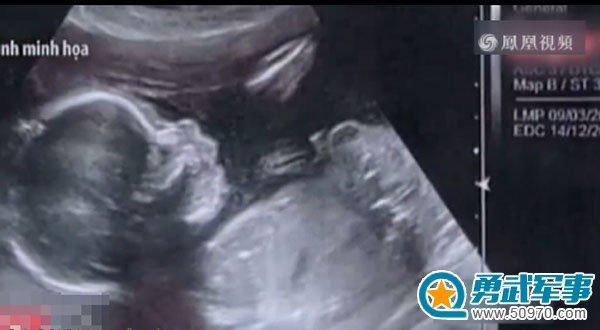

调查人员发现,该女子为逃避死刑,于去年8月以2000美元的价格偷偷买下一名男囚犯的精液,进行自我受精并最终怀孕。今年4月孩子出生后,她将获得减刑,改为终身监禁。在此案中,有四名狱警因涉嫌玩忽职守而被停职。

美国《世界邮报》援引英国《泰晤士报》的报道称,现年42岁的阮氏慧在2012年犯下越南史上最大的一宗毒品案,这也是涉及死刑犯数量最多的案件。她于 2014年被判处死刑。另据美联社称,她曾上诉,但被法院驳回。尽管如此,现在她仍然可以免于一死,因为越南刑法禁止对孕妇及子女不满3周岁的女性使用死刑,需将死刑改为终身监禁。